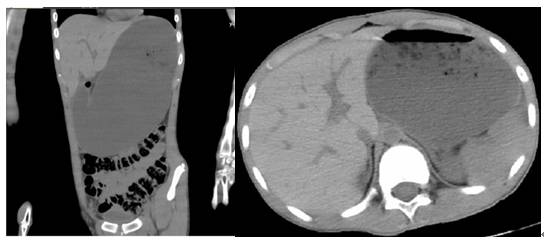

术后第4天,患者腹胀、腹痛较前明显加重,伴剧烈呕吐。肛门塞开塞露后有少量排便。查体:腹膨隆,腹肌稍紧张,无明显压痛及反跳痛。急诊行全腹部平扫:胃及十二指肠近段扩张,内见大量内容物淤积,并可见液平。诊断:“十二指肠近段梗阻提示,请结合临床。”(图3)。请普外科急会诊:考虑胃肠排空障碍,予以禁食、胃肠减压,生长抑素微泵维持及通便药物治疗。

图3. 全腹部CT平扫,胃及十二指肠近段扩张,内见大量内容物淤积,并可见液平。